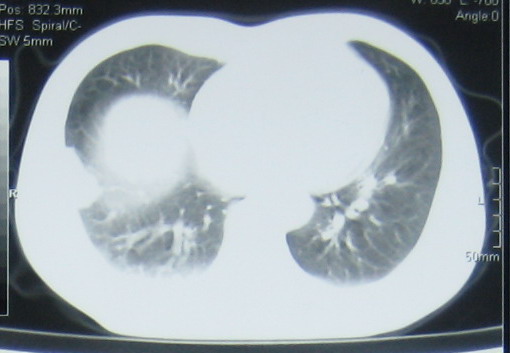

病个42岁,呼吸时胸痛,不可平卧!

右下肺外基底段感染病灶伴局部胸膜反应增厚粘连

考虑右肺下叶外基底段感染病变伴局部胸膜反应;建议抗炎治疗后复查。

不除外肺梗死

警惕肺梗死

1、肺梗塞,可产生附近胸膜的纤维素性炎症,出现与呼吸有关的胸膜性疼痛。2、右下肺外基底段炎症。

考虑右下肺外基底段感染病灶伴局部胸膜反应增厚粘连,抗炎治疗后复查。